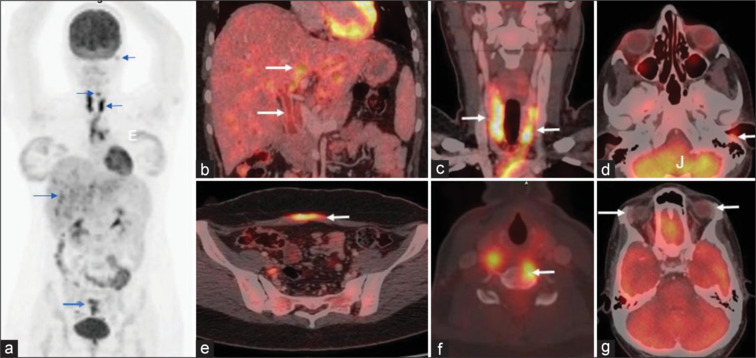

Langerhans Cell Histiocytosis (LCH) is a rare neoplasm of the hematopoietic system, characterized by the clonal proliferation of Langerhans cells and it is more common in children. We present two interesting adult cases of LCH, diagnosed with the help of FDG PET-CT imaging which is often challenging to diagnose due to its rarity and nonspecific clinical presentation.